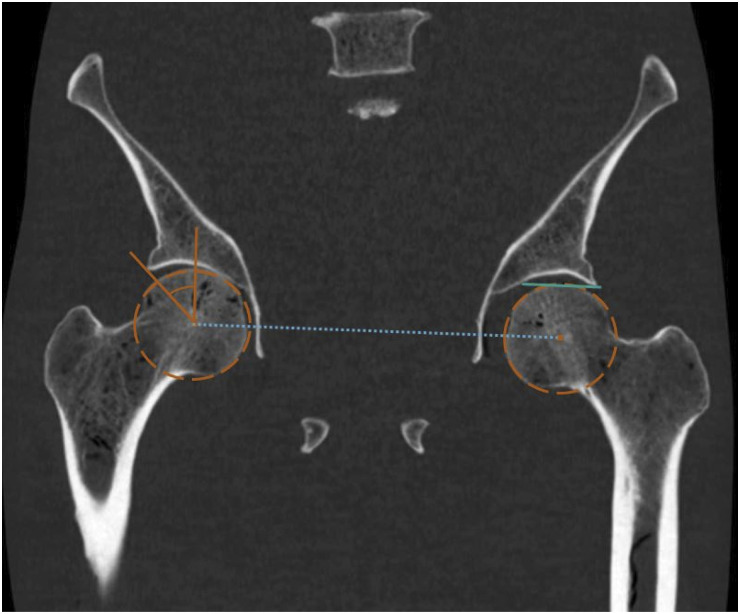

Purpose: To estimate agreement between measurements of lateral center edge angle (LCEA) and acetabular inclination angle (AIA) made, respectively, on Computed Tomography (CT) scans by humans and radiographs analyzed by an algorithm. To estimate impact of pelvic rotation on agreement between CT and radiographic measurements.

Abstract Image